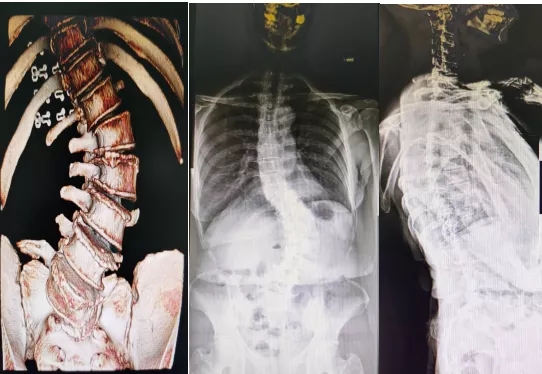

53岁的韦红(化名),腰背部疼痛十余年,近两年明显加重,行走不到100米就要蹲下来休息,给生活带来了极大不便。她多处求医后无果,慕名来到附属医院脊柱、骨病外科,医生通过仔细查体、完善相关检查后认为患者存在退变性脊柱侧凸,腰椎管狭窄症和腰5-骶1滑脱。

可能需要同时处理腰椎管狭窄和脊柱侧凸,而退变性脊柱侧凸不仅有腰椎侧凸畸形,同时腰骶部也有畸形,如果处理不好,患者可能会出现躯干失衡。

患者手术前影像

这样的脊柱畸形手术不同于青少年特发性脊柱侧凸,青少年的脊柱柔韧性往往较好,不需要截骨手术,而成人的脊柱畸形往往很僵硬,需要对弯曲最大的部位进行截骨矫形,手术时间长,出血量也大,手术风险就更大,需要更高的手术技巧才能完成。